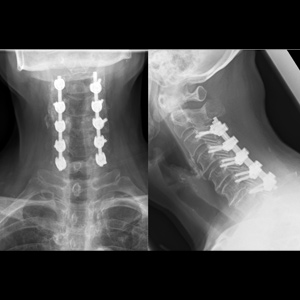

Spinal stenosis (Lumbar) Spinal stenosis (Cervical) Spinal stenosis (Thoracic) Lumbar Disc Herniation Spondylolisthesis Cervical Foraminal Stenosis Vertebroplasty Lumbar Fusion Anterior Cervical Fusion (ACDF) Posterior Cervical Fusion Thoracic Fusion Revision Lumbar Fusion Surgery Facet Joint Cyst Spinal Tumour Minimally Invasive Lumbar Fusion (XLIF) Minimally Invasive Lumbar Fusion (ALIF) Lumbar Fusion (TLIF) Thoraco-lumbar Fusion Lumbar Corpectomy Complex Lumbar Spine Surgery (Spino-pelvic fixation) Complex Cervical Spine Surgery Complex Thoracic Spine Surgery Occipito-cervical Fusion Minimally invasive surgery for thoracic disc herniation Other Related Topics